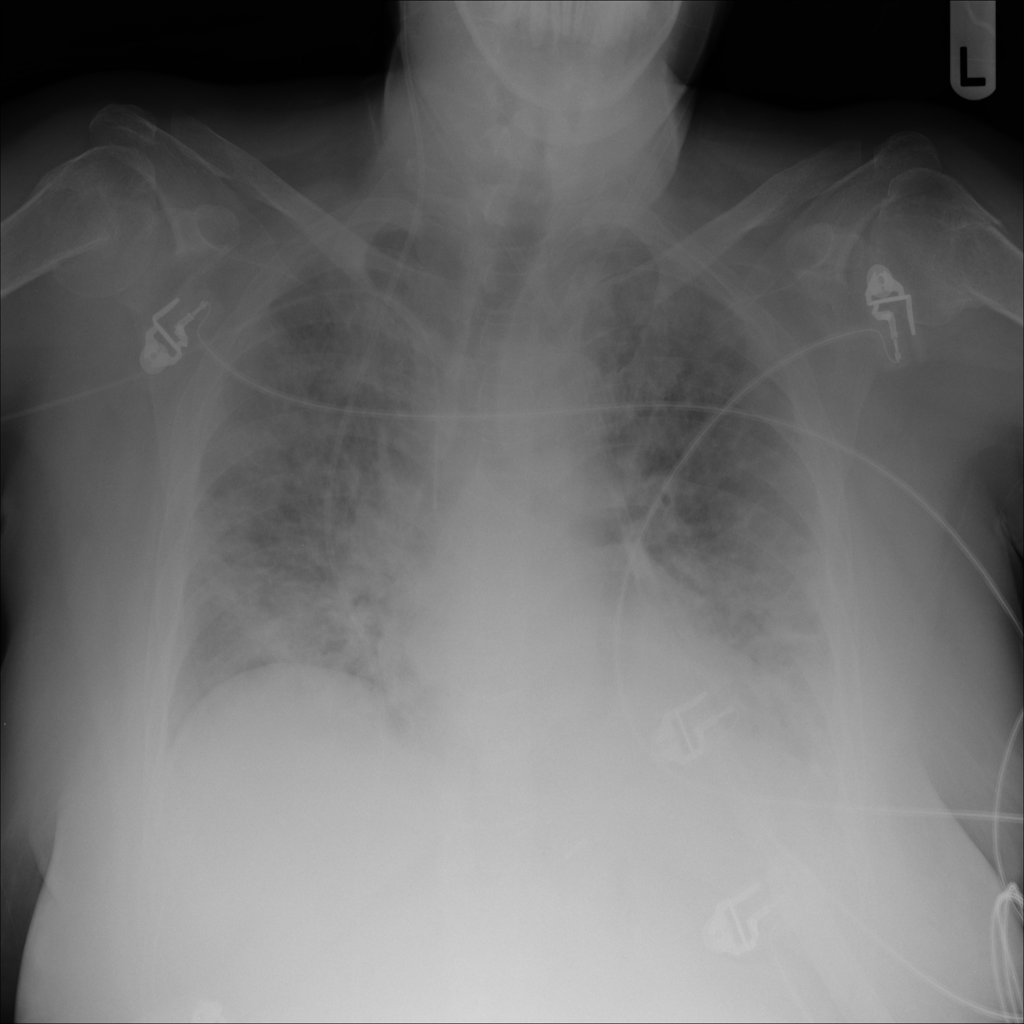

Showing up to 90 reference images for Pneumonia.

PAT-B3C3 · IMG-001Pneumonia

PAT-B3C3 · IMG-001

PA